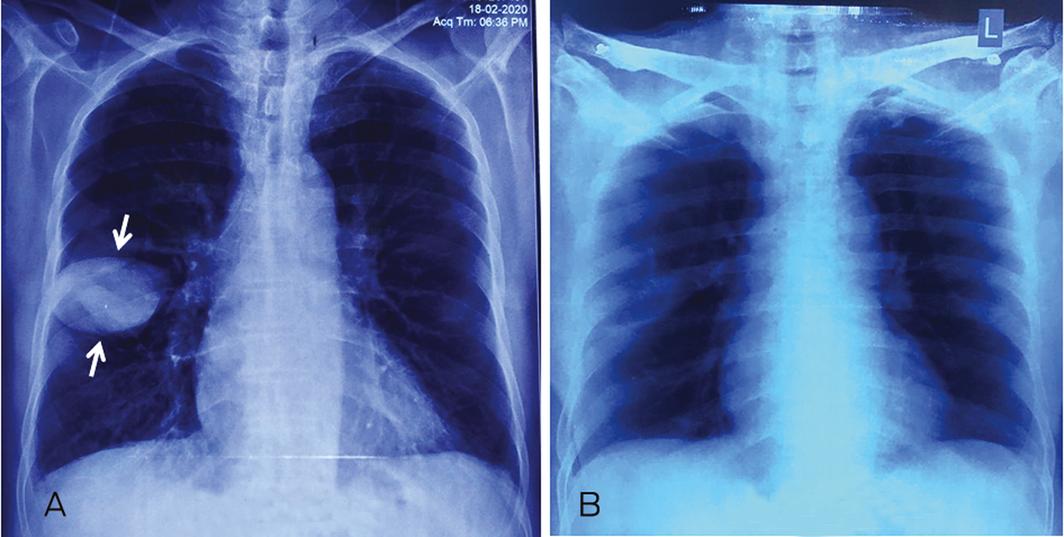

A 68‐year‐old man with diabetes presented with progressive dyspnoea of one month duration. On examination, he had atrial fibrillation with rapid ventricular response, raised jugular venous pressure, presence of pedal oedema, crepitations in chest, and left ventricular third heart sound. Chest x‐ray revealed a well defined oval shaped opacity (the “phantom tumour”) in the transverse fissure of the right lung (Figure, A; white arrows), which resolved completely after 4 days of diuretic therapy (Figure, B). Echocardiography revealed global hypokinesia of the left ventricle with a left ventricular ejection fraction of 28%. A phantom tumour is a localised collection of fluid in the lung fissures (mostly in the transverse fissure) in patients with heart failure.1 The underlying mechanism is thought to be repeated episodes of pleuritis.1